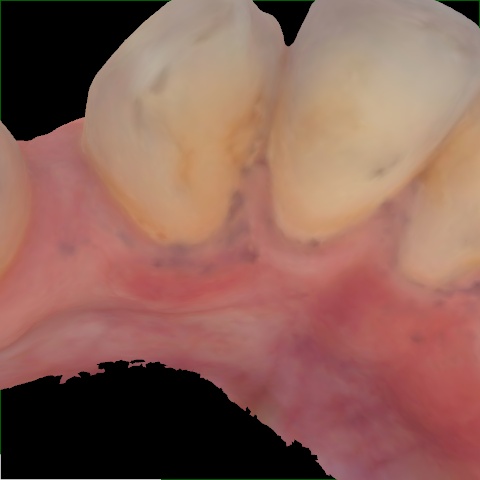

Image 317 / 400

NHD20794

Annotated as "Good"

Original Image Rendering Image